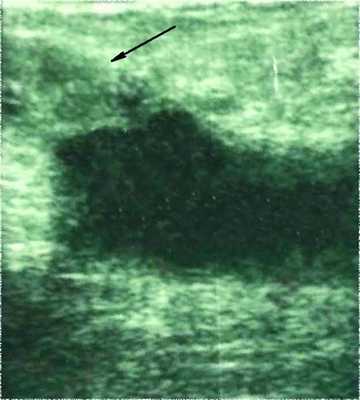

Ультразвуковое ангиосканирование вен нижних конечностей (УЗАС): правая большая подкожная вена тромбирована на всем протяжении до сафено-феморального соустья (рис. 1, а). Рисунок 1. Ангиосканограммы больной С. а - тромб в приустьевом отделе большой подкожной вены (стрелка). Глубокие вены обеих нижних конечностей проходимы, клапаны их состоятельны. Перфорантные вены не тромбированы.